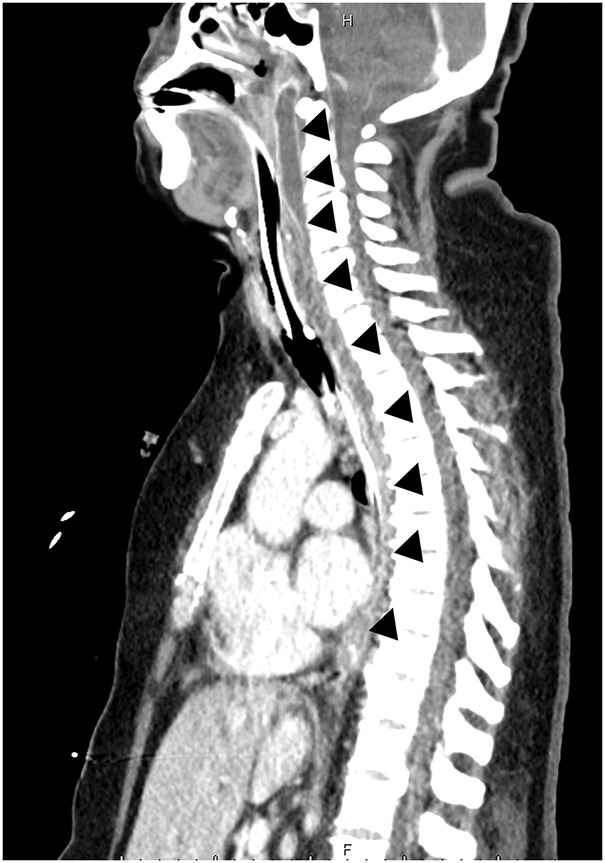

Case presentation: A female patient with morbid obesity (body mass index, 41 kg/m2) and a heavy smoking habit underwent laparoscopic sleeve gastrectomy and was discharged without any immediate postoperative complications. Six weeks later, the patient presented with severe chest and back pain that required continuous fentanyl injection for pain management. Initially, staple line leakage, commonly observed after sleeve gastrectomy, was suspected. However, her condition progressively worsened, and she was admitted to the ICU. An enhanced abdominal CT scan extending to the cervical region revealed a cervical abscess extending to the lower mediastinal region. The patient was diagnosed with descending necrotizing mediastinitis. Given the rarity of this disease, we hypothesized that her smoking habits exacerbated the piriform fossa injury caused by the calibration tube used during gastrectomy. Following the diagnosis, emergency abscess drainage surgery was performed, and the patient was successfully treated.

Conclusions: This is the 1st reported case of descending necrotizing mediastinitis as a fatal complication of laparoscopic sleeve gastrectomy, which was identified and treated successfully owing to the timely and expanded use of an enhanced CT scan that included the cervical region. Traditionally, the cervical area has not been routinely examined when diagnosing complications following abdominal surgery, underscoring the importance of a comprehensive imaging approach from the neck to the abdomen to detect complications after sleeve gastrectomy.